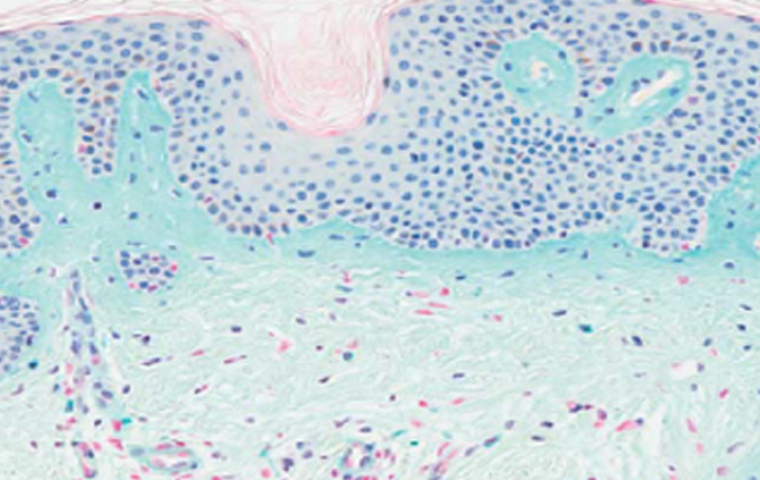

겔은 흡수되고 CaHA 입자는 자연 분해되어

최종적으로 내 콜라겐만 남습니다.

5가지 재생 성분이 피부 속 코어를 채워주어,

시간이 지나도 콜라겐이 생성되고 자연스러운 볼륨이 오래 유지됩니다.